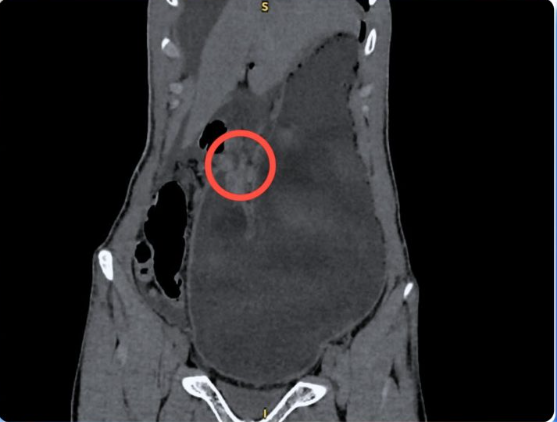

Tại khoa Cấp cứu, các bác sĩ ghi nhận cơn đau không thuyên giảm, bệnh nhân toát mồ hôi, bụng chướng. Qua thăm khám và chụp CT-scan ổ bụng, kết quả cho thấy có nhiều khí và dịch tự do trong ổ bụng, dạ dày giãn lớn, thành hang môn vị dày bất thường và chỉ số bạch cầu tăng cao.

BS.CKII Nguyễn Vũ An – Trưởng khoa Ngoại Tổng quát chẩn đoán bệnh nhân bị viêm phúc mạc toàn thể do thủng ổ loét môn vị tá tràng và hẹp tá tràng hoàn toàn – một cấp cứu ngoại khoa nguy hiểm, đe dọa trực tiếp tính mạng nếu không phẫu thuật kịp thời.

Hình ảnh CT cho thấy bệnh nhân bị thủng ổ loét môn vị tá tràng - Ảnh BVCC

Ê-kíp nhanh chóng hội chẩn khẩn và tiến hành mổ cấp cứu. Trong quá trình phẫu thuật, bác sĩ phát hiện lỗ thủng mặt trước môn vị – tá tràng khoảng 2cm, kèm theo lượng lớn dịch đục lan khắp ổ bụng.